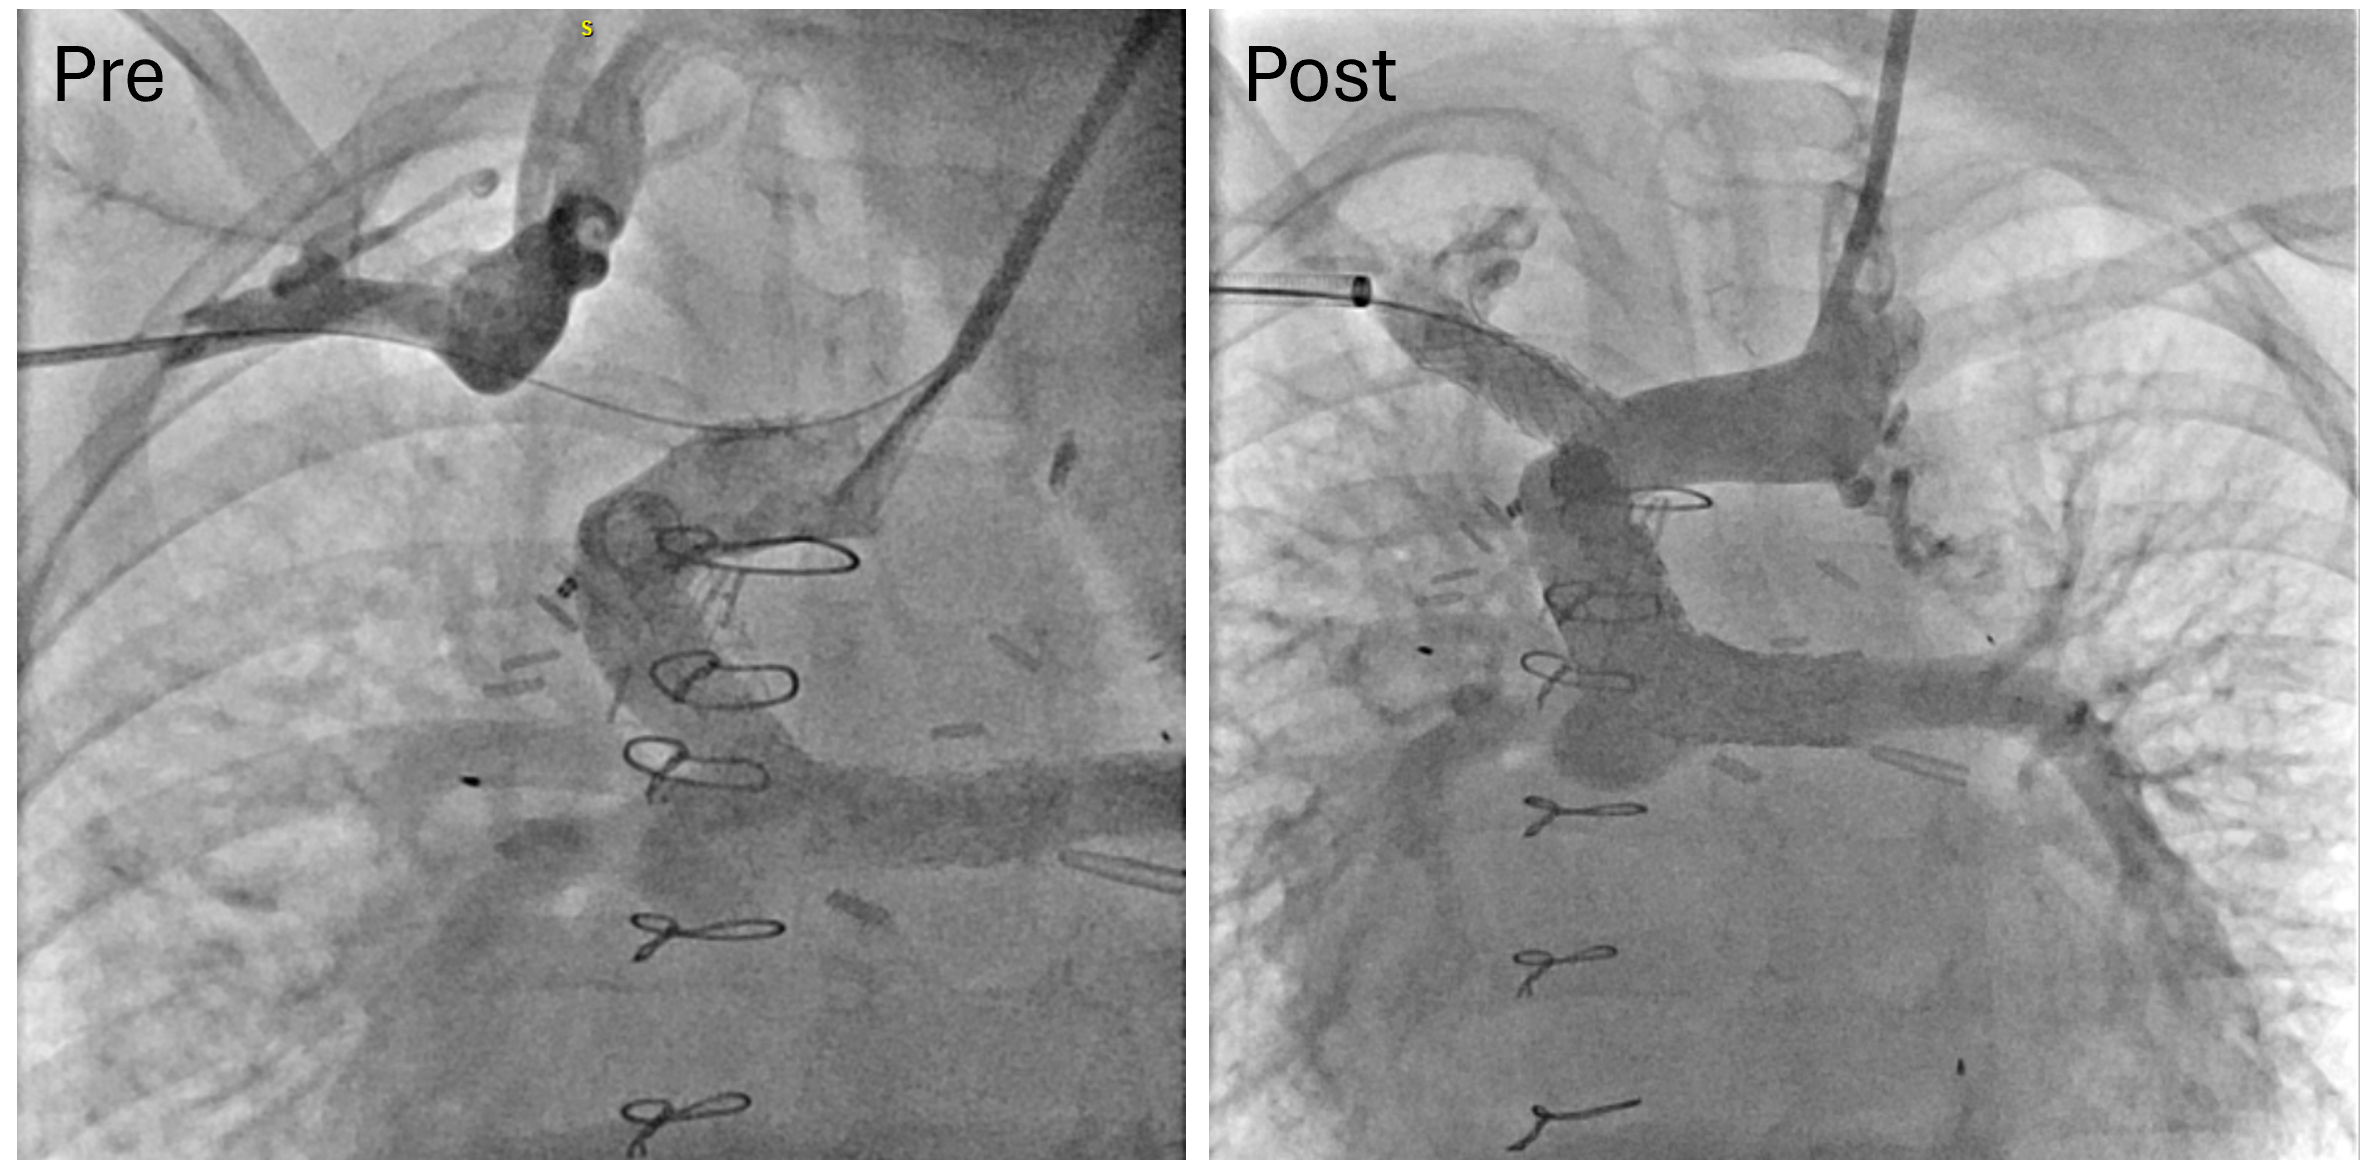

From a procedural standpoint, general anesthesia was utilized in 17 of the 23 procedures, while monitored anesthesia care was provided for the remaining 6 procedures. The patients typically underwent right heart hemodynamic catheterization, coupled with angiography for those with RVOTO, PAS, and SVS (Figures 1-3, pre). Additional retrograde left heart hemodynamic catheterization and angiography were performed for the patients with CoA (Figure 4, pre). The delivery sheath was as small as 7-French (Fr) in the femoral vein for the patients with RVOTO, PAS, and SVS, and 8-Fr in the femoral artery for patients with CoA, with ultrasound confirmation of a femoral arterial diameter greater than 3 mm prior to access in smaller patients. Stent size and pre-mount balloon diameter were chosen based on targeted pre-/post-stenotic vessel diameter, in addition to minimum waist diameter to allow secure delivery. Length was determined for adequate coverage of the targeted lesion. Rapid right ventricular pacing was performed only for CoA stent implantations. Selective post-implantation dilation with a non-compliant balloon was performed as needed to achieve the targeted diameter. Post-implant ultra-high-pressure dilation (≥ 20 atm) was performed on 8 stent grafts for full expansion (Table 2). Post-implantation angiography (Figure 1-4, post) and hemodynamic measurements were analyzed for all cases (Table 2).

The low profile of the stent graft is also advantageous for small pediatric patients because it minimizes the risk of access site complications. We have previously detailed the technique for transcatheter palliation for CoA in young children (Figure 4).4,9 The 8L configuration, pre-mounted on an 8-mm balloon, is designed to go through a 7-Fr sheath. Recently, a new set of lower profile stent grafts has become available, with some designed to go through a 6-Fr sheath.